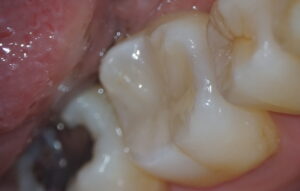

治療後

写真左:充填後の歯、写真右:治療中の歯